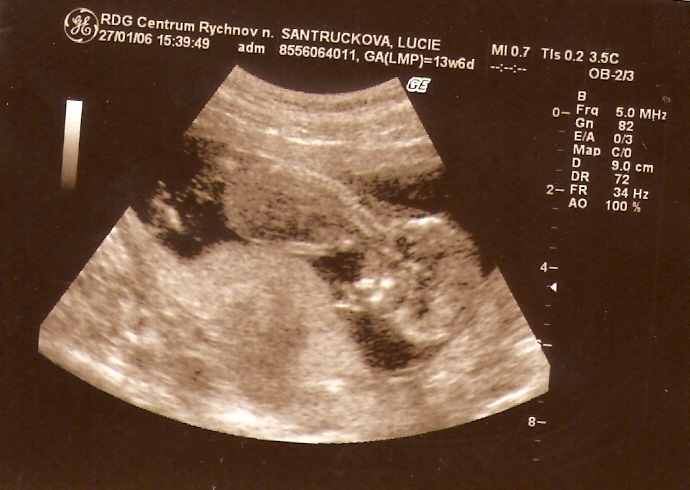

...27. LEDNA 2006 /14. týden/ mě poprvé viděli na ultrazvuku...zrovna jsem měl škitavku a pouhých 9 cm...